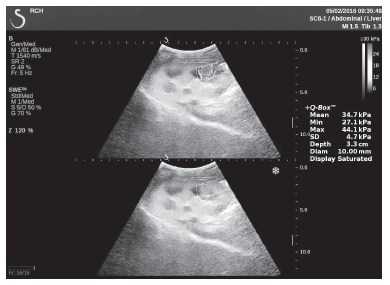

Клинический пример из второй группы. Пациент К. перенес операцию пересадки почки от живого родственного донора. Трансплантат в левой подвздошной области. Индекс резистентности в междольковых артериях составил 0,70 (рис. 5). В сегментарных артериях индекс резистентности составил 0,66 (рис. 6). Показатели жесткости паренхимы почечного трансплантата при режиме УЭСВ составили от 31,6 до 36,9 кПа (рис. 7-9).

Рисунок 8. Исследование в режиме ультразвуковой эластографии сдвиговой волны у пациента К.: жесткость паренхимы в зоне нижнего полюса почечного трансплантата 34,7 кПа